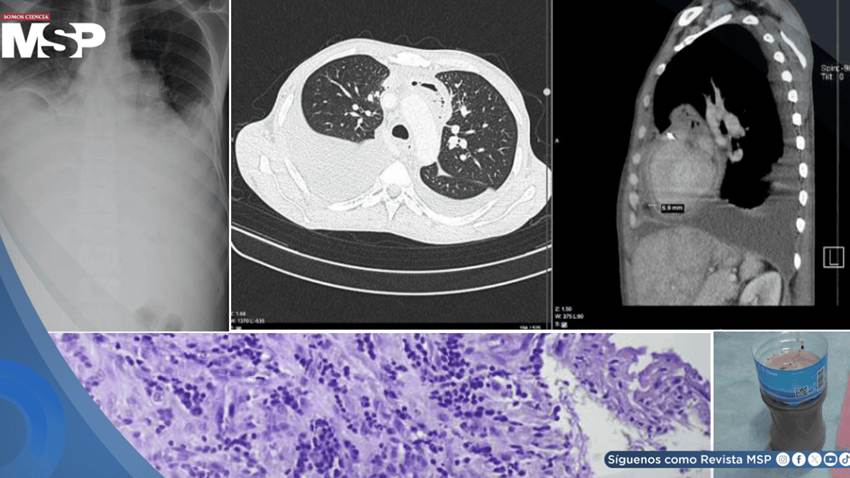

Inicialmente, sus síntomas hicieron pensar a los médicos en una neumonía combinada con una insuficiencia cardíaca. Las radiografías confirmaron la presencia de una gran cantidad de líquido en ambos pulmones.

Los médicos descubrieron que el problema no solo estaba en sus pulmones, sino también en el corazón: un ecocardiograma reveló que este órgano estaba siendo comprimido por una acumulación de líquido en el pericardio, la membrana que lo recubre. Esta condición, conocida como taponamiento cardíaco, es una emergencia.

De inmediato, se realizó una pericardiocentesis, un procedimiento para drenar el líquido que oprimía al corazón. Para sorpresa de los médicos, se extrajeron 950 mililitros de pus, lo que confirmó que el paciente sufría de una pericarditis purulenta, una infección grave en el saco pericárdico.

Frasco lleno de pus extraído tras la pericardiocentesis.

A pesar de que los análisis específicos del pus (como cultivos y la prueba GeneXpert) no lograron identificar la bacteria responsable, el nivel extremadamente bajo de glucosa en el líquido era un indicio claro de infección.

Según los autores (Proches, V. et al) el análisis final del tejido pericárdico mostró una inflamación crónica consistente con una infección, pero, una vez más, no se visualizaron los bacilos de la tuberculosis bajo el microscopio.